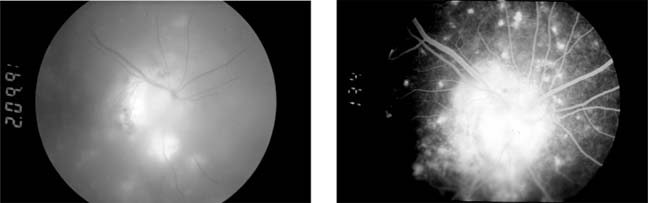

Impairment of the blood supply to the optic disk produces sudden visual loss, usually with an altitudinal field defect and pallid swelling of the optic disk. The primary abnormality is complete or partial interruption of the choroidal blood supply to the disk, while the retinal capillaries on the surface of the disk appear dilated. Fluorescein angiography confirms the circulatory alterations (Figure 15-2). Pathologic studies show infarction of the retrolaminar region of the optic nerve. The explanation for the vulnerability of the short posterior ciliary vessels supplying this region is unknown. Optic disk infarction is often caused by giant cell arteritis in old age and by hypertension and arteriosclerotic disease in middle age. Small optic disks are particularly prone to infarction.

Figure 15-2

Figure 15-2: Ischemic optic neuropathy. Sudden visual loss in a 48-year-old man produced a complete inferior altitudinal field loss. Left: Fluorescein angiogram shows impaired filling of the upper part of the disk with dilation of retinal capillaries at the lower part of the disk. Right: Photograph 10 minutes after injection shows leakage of dye mainly at the lower part of the disk.